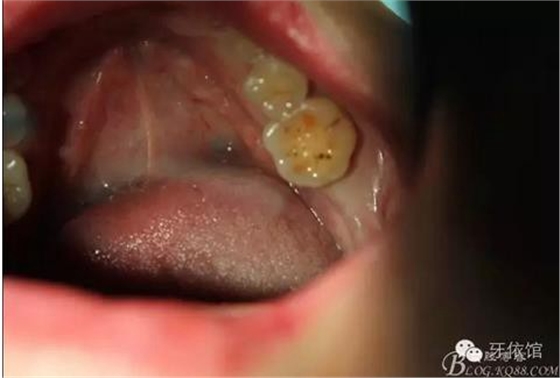

患者女,45歲,右上6于多年前牙髓失活后充填,未作冠,術前不久,進食時不幸劈裂。檢查發(fā)現(xiàn):右上6充填物脫落,近遠中向縱劈,x光見根管內(nèi)無充填物。同時有右上7、右下7缺失。計劃:右上6,7,右下7種植修復。右上6為即可種植,同時做內(nèi)提。

上6分根